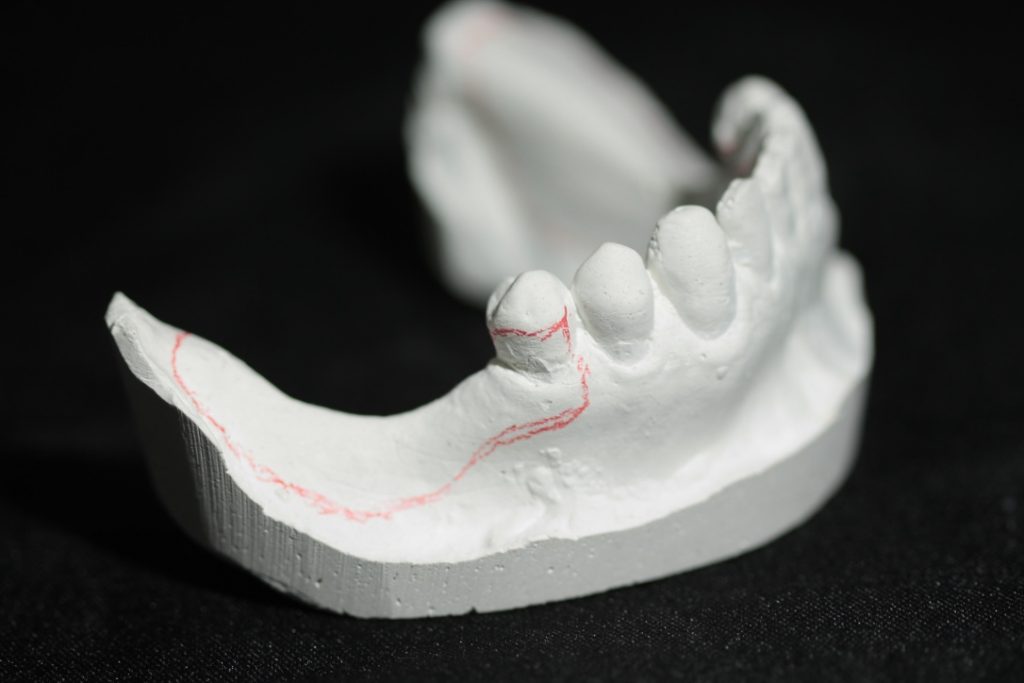

Design & Blockout Example

Watch an example of how to design and block out a difficult Kennedy Class I case.

Design for a case with long free end saddles.

The angulation of the teeth present a challenge with path of insertion.

Adding too much blockout could work against you in this case.